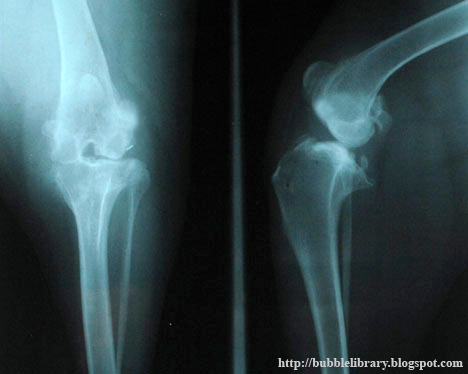

Broken bones - bones break under varying degrees of pressure according to age, health and other circumstances. They are made of hard, strong connective tissue and normally resist considerable force before breaking or fracturing. But when a bone has been softened by disease or grown fragile with age, fractures may follow very minor accidents or even occur spontaneously (pathological fractures). The bones of children are not fully mature and are still relatively flexible. In childhood a severe blow or fall often results in a (greenstick) fracture, in which the bone appears to bend but does not completely break into two separate pieces. An impacted fracture occurs when the broken ends of the bone appear to be jammed together by the force of the injury. A comminuted fracture is one in which the ends are shatted into many pieces. A fracture is called simple (closed) when the overlying skin is not broken, or compound (open) when the bone is exposed. All fractures attempts to heal themselves by producing new tissue to join the broken pieces together. At first this tissue is like putty and easily injured. So, generally a fractured limb should be straightened, immobilized and protected by a plaster cast while the healing takes place. In time the new tissue, or fracture callus, changes into mature bone.